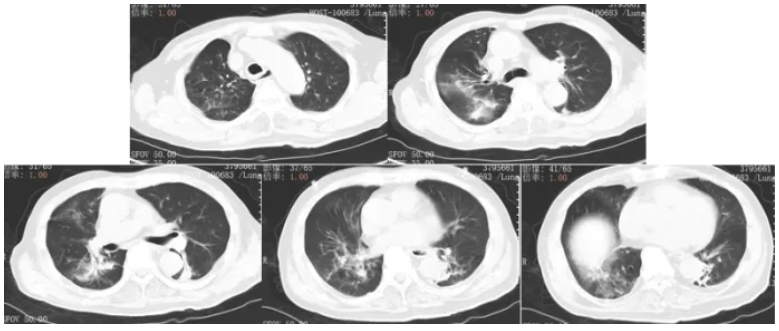

6. 影像学检查(2025-01-05,急诊)

肺部CT(图1): 肺气肿; 双肺新增多发感染、双肺间质性病变; 左上肺实性小结节(较前增大, 考虑炎性灶);右下肺钙化灶、气管旁憩室。

图1 患者入院胸部CT(2025-01-05)